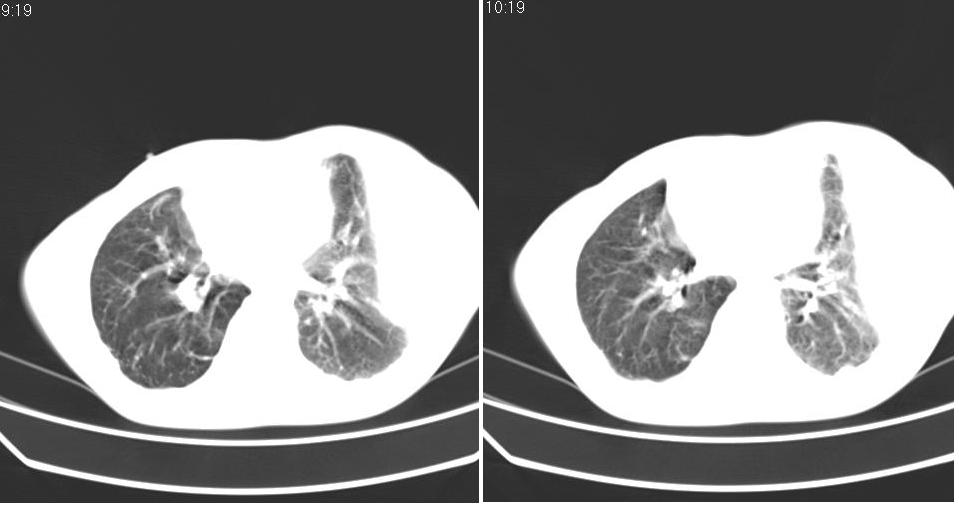

以下是引用苯小孩在2007-6-27 15:09:00的发言:[br]考虑:1、右肺继发性肺结核.2、双侧包裹性积液<胸腔及叶间>3、双侧局部胸膜增厚.[br]建议胸水化验检查.

以下是引用yanghaochen88在2007-6-27 15:08:00的发言:[br]双肺上野散在粟粒状影、包裹性积液、胸膜增厚粘连、叶间积液---tb,至于分型还得结合病史体征细究妥当些。